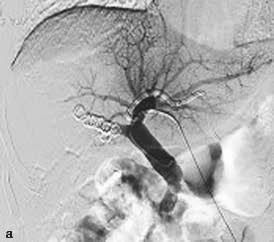

PVE栓塞材料多样,包括弹簧微钢圈、明胶微球、吸收性明胶海绵、凝血酶、超乳化碘油、纤维蛋白胶、无水乙醇、聚乙烯醇颗粒、氰基丙烯酸正丁酯(N-Butyl cyanoacrylate,NBCA)等,多种材料个体化联合应用能够增强栓塞效果(图2-5-1)。

图2-5-1 采用不同栓塞材料实施PVE

A、a.弹簧微钢圈栓塞门静脉右支;

B、b.氰基丙烯酸正丁酯栓塞门静脉右支和Ⅳ段支;

C、c.微钢圈联合氰基丙烯酸正丁酯栓塞门静脉右支。